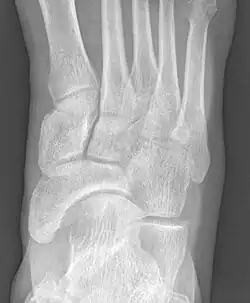

X-ray of the foot showing an accessory navicular bone

An accessory navicular bone is an accessory bone of the foot that occasionally develops abnormally in front of the ankle towards the inside of the foot. This bone may be present in approximately 2-14% of the general population and is usually asymptomatic.[1][2][3] When it is symptomatic, surgery may be necessary.

Radiological images